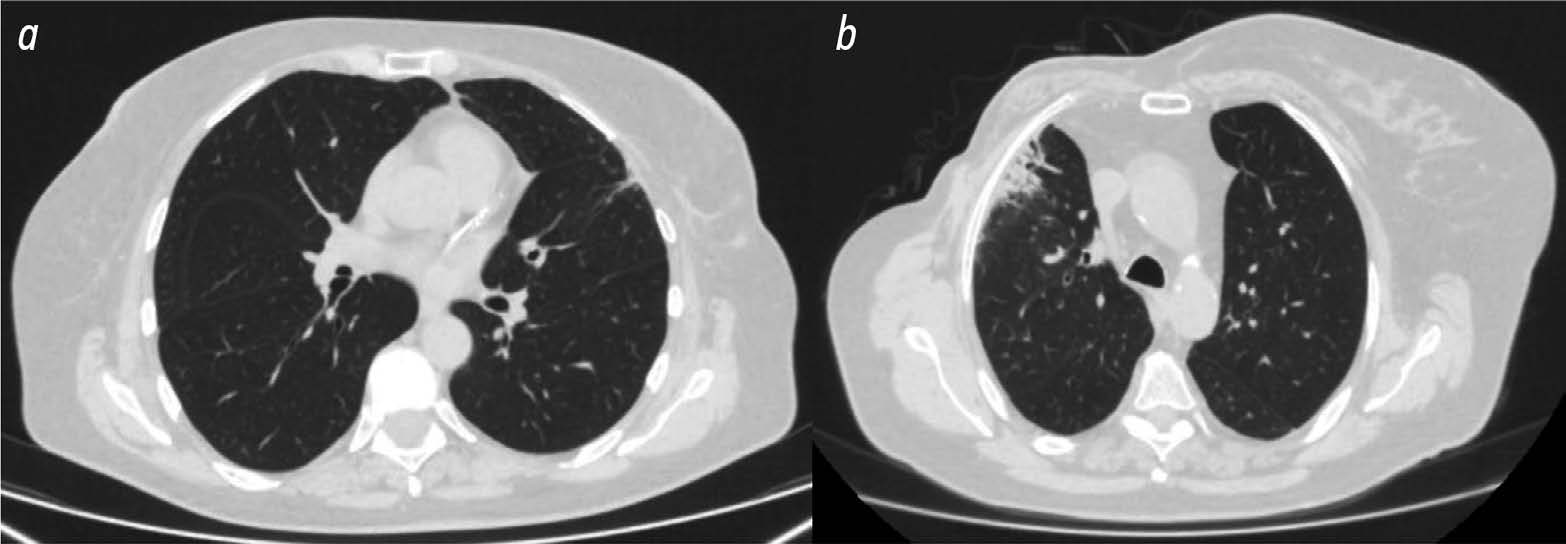

The role of computed tomography in the differential diagnosis of an intracardiac mass of the mitral valve: a case series

Abstract

The differential diagnosis of an echocardiographically detected intracardiac mass in the mitral annulus can be challenging and usually requires a multimodal approach. This type of lesion is very often associated with subvalvular calcification of the mitral valve. The rare, caseous, variant is the most difficult to diagnose. This case series highlights the clinical significance of computed tomography in detecting and characterizing subvalvular mitral annular calcification when other modalities, particularly echocardiography, are inconclusive. The aim of this article was to raise awareness among specialists of the classic signs of caseous subvalvular calcification of the mitral annulus when visualized with different modalities. Special attention is also given to providing a differential diagnostic series that identifies features that differentiate subvalvular calcification of the mitral annulus from other conditions at this site. Healthcare professionals need to be aware of these mitral valve lesions in order to predict possible associated complications and plan a treatment strategy that may help avoid unnecessary surgical procedures in some cases.

893-901